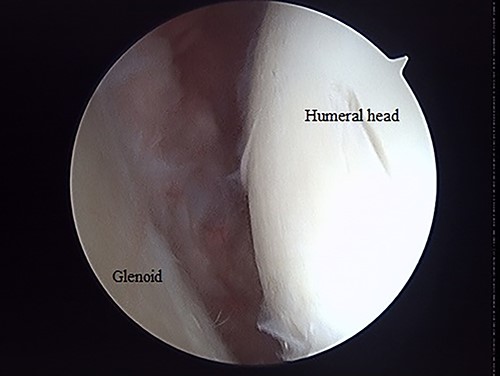

Postoperative radiographic and CT evaluations showed reduced fractures on the humeral head and surgical neck (Fig. 7). At 24 months of postoperative follow-up, radiographic and CT evaluations showed no signs of osteoarthritis or reimpression (Fig. 8). Two years after the primary surgery, we performed implant removal at the patient’s request (Fig. 9). When performing implant removal, we additionally performed a second-look evaluation with arthroscopy to assess the degree of healing in the joint. We noted no impression or exposure of cartilage callus on either side of the humeral head or glenoid (Fig. 10).

Posterior endoscopy of the shoulder joint showing no reimpression or exposure of subchondral bone.